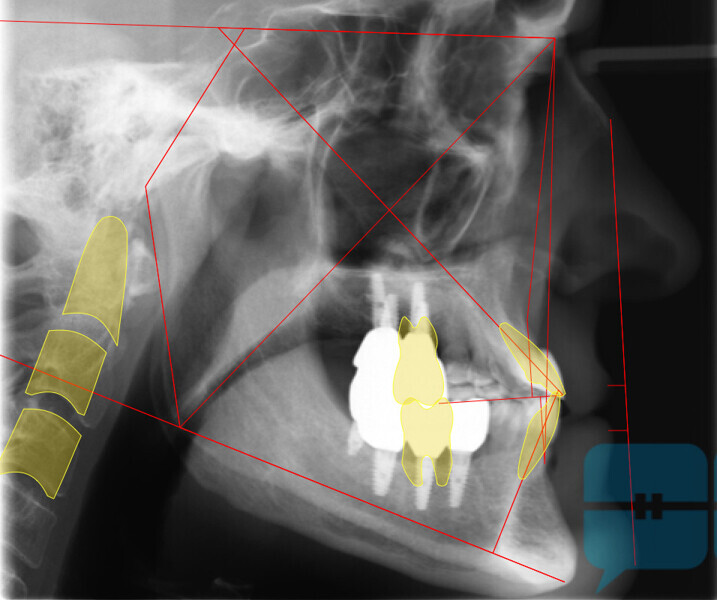

This patient, like all patients requiring interdisciplinary rehabilitation, had to first undergo periodontal treatment and caries restoration (Fig. 17). At the same time, it was important to rehabilitate swallowing with Froggymouth and relax the masticatory muscles and relieve the TMJs with an occlusal device. We could then study the orthodontic treatment plan using Invisalign ClinCheck (Align Technology) and showed the treatment plan to the interdisciplinary team and to the patient (Fig. 18). We were then able to create the correct sequence of orthodontic treatment, bone augmentation and implant surgery needed for the posterior edentulous spaces.

After the first phase of aligner treatment, we had achieved better inter-arch coherence, better maxillary arch expansion, and some space for improving the anterior tooth proportions restoratively (Fig. 19). We then temporarily restored the anterior teeth directly with composite, closing the spaces, improving the tooth proportions and further increasing the maxillary arch expansion (Fig. 20). We used restorative arch expansion to reduce the orthodontic destabilisation of the teeth to achieve the correct inter-arch coherence and retain the teeth in the cortical bone.38 A refinement aligner phase was undertaken to improve the final alignment of the gingival zenith and to improve the inter-arch coherence (Fig. 21). The periods of the first orthodontic phase and of the refinement were used to augment the mandibular and maxillary bone and to place the implants (Fig. 22). At the end of the orthodontic treatment, the case was finalised with ceramic veneers in the anterior area and temporary restorations on the implants in the posterior area (Figs. 23–26).

The provisional phase of about four months was important to allow the peri-implant tissue to mature and to teach the patient to chew correctly with chewing gum, cotton rolls and silicone masticatory sticks. This is fundamental training for the patient to achieve the correct alternating unilateral masticatory cycle needed to obtain the ideal rehabilitation of the masticatory system. We wanted the patient to achieve ideal masticatory and swallowing function. After sufficient rehabilitation time, we finalised the case with posterior zirconia crowns screwed on to the implants (Fig. 27).26